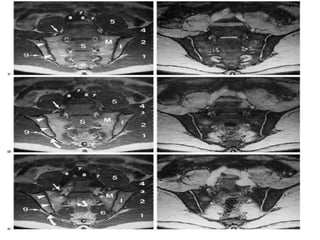

MR examination of sacroiliac joints, images: T1- (A), T2 TIRM ;Turbo inversion recovery

magnitude (TIRM) (B), T1FSCE-weighted (C): bone marrow edema, more pronounced in

right sacroiliac joint, particularly in the iliac bone as well as erosions undergoing strong

enhancement following administration of contrast medium, contrast enhancement and

thickening of synovial membrane in the sacroiliac joint (synovitis), inflammation of right

sacroiliac joint capsule (capsulitis), subchondral sclerosis